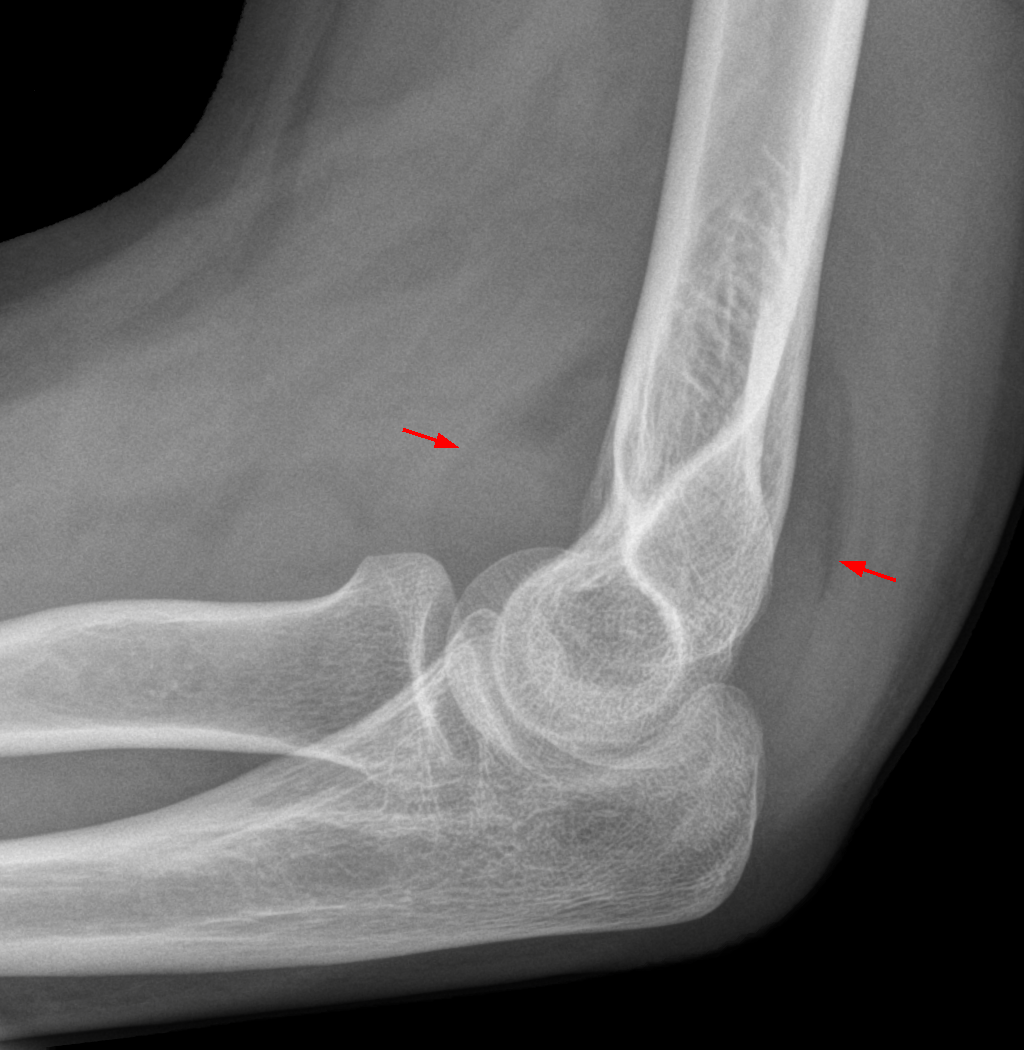

Правило «Fat Pad Sign»

Fat Pad Sign: анатомические основы и интерпретация

• На боковой проекции рентгена в норме имеют вогнутые контуры.

• Fat Pad Sign+: Выпуклые или треугольные («парусообразные») контуры → признак выпота/гемартроза (Gupta et al., AJR, 2020).

Клиническая значимость:

• У взрослых: В 70–80% случаев связан со скрытыми переломами мыщелков плеча/бедра/большеберцовой кости (Donnelly et al., Journal of Bone and Joint Surgery, 2021).

• У детей: Может указывать на переломы Salter-Harris I–II без смещения (NICE Guidelines, 2022).